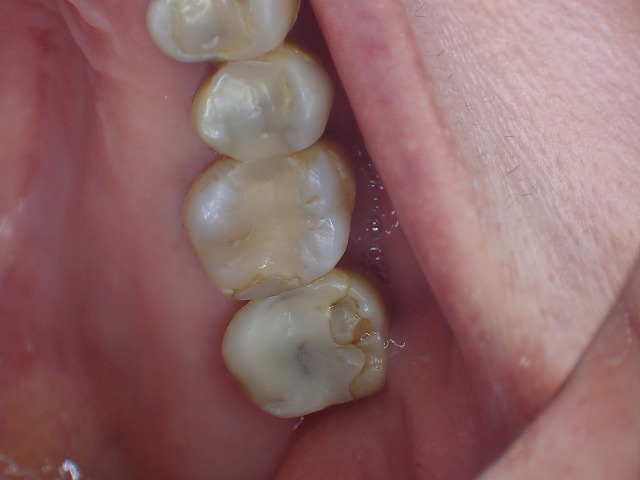

顔面に対して水平垂直も位置決めをして

左右対称に形態修正後、磨きをかけました。

よいものは長持ちです。

20年以上前の補綴物ですが綺麗になりました。

この方の場合は歯周病処置も含めて

定期的にお手入れすることがおすすめです。